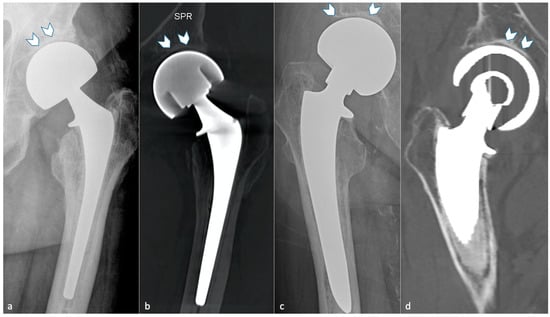

4.11. Heterotopic Ossification